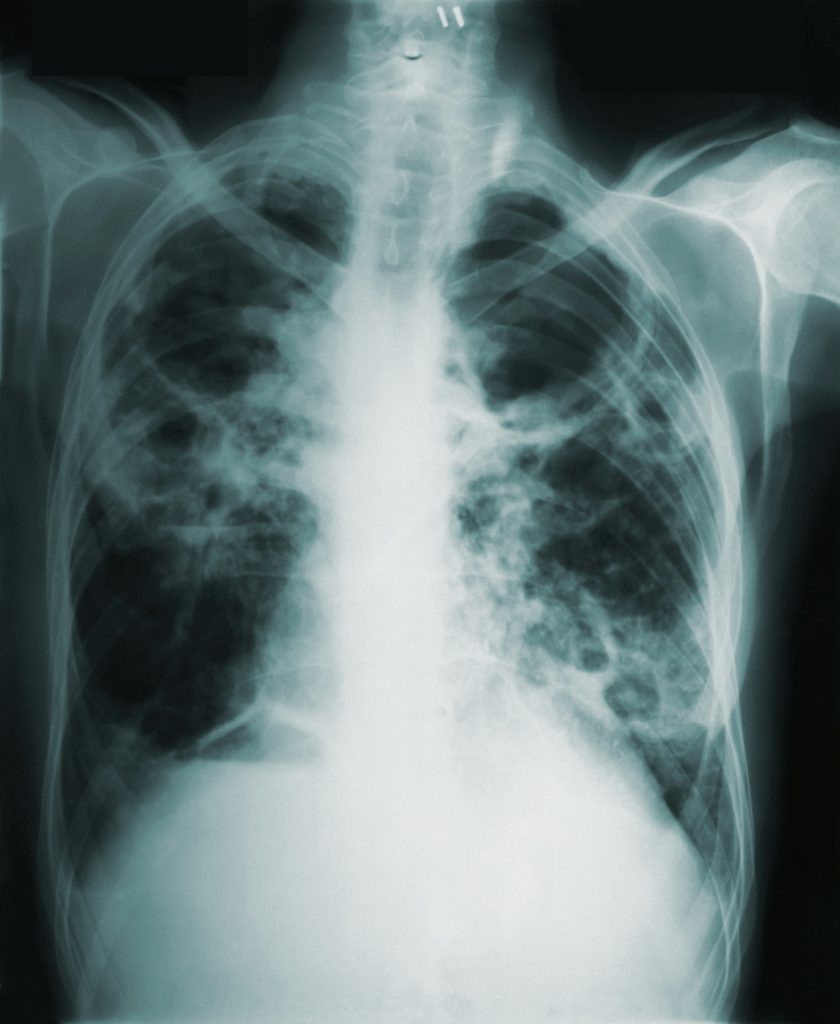

Legionnaires’ disease is often confused with other pneumonia-like illnesses, as many symptoms overlap for both conditions. It is even indistinguishable from typical pneumonia on a chest x-ray.